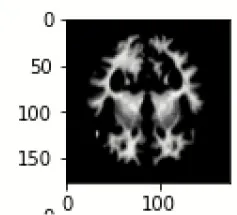

The database used in this study consists of a total of 6,200 AD images that are retrieved from the Kaggle database. It comprises grayscale images of 896 MD, 64 Mod D, 3,200 ND, and 1,966 VMD images, with a dimension of (208 × 176 × 3) pixels. The dataset for evaluation is divided in such a way that 80% of the image samples are utilized for training the model and the remaining 20% are utilized for testing the model (Filipovych et al., 2011). Figure 2 shows the database of MRI images. Table 2 shows the publicly available AD dataset.

FIGURE 2

www.frontiersin.org

Figure 2. Alzheimer's disease: (A) M.D, (B) Mod.D, (C) N.D, and (D) V.M.D.